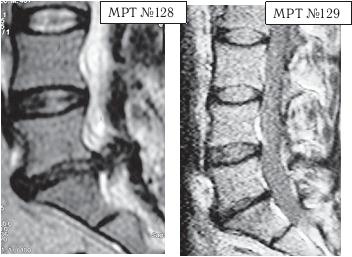

На МРТ № 128 наблюдается состояние поясничного отдела позвоночника после операции: рецидив грыжи межпозвонкового диска в сегменте LV-Sr с отрывом секвестра и его миграции в краниально-дорсальном направлении, разрыв задней продольной связки.

На МРТ № 129 наблюдается состояние поясничного отдела позвоночника после лечения методом вертеброревитологии: отсутствие грыжи межпозвонкового диска в сегменте L — S. В межпозвонковых дисках в сегментах LIV-LV, L — SI наблюдается процесс репаративной регенерации.

На МРТ № 130 наблюдается состояние поясничного отдела позвоночника после двух хирургических операций: рецидив грыжи межпозвонкового диска в сегменте LV-SI.

На МРТ № 131 наблюдается состояние поясничного отдела позвоночника после лечения методом вертеброревитологии.

Рецидив грыжи межпозвонкового диска после двух хирургических операций — и это у молодого человека в возрасте 16 лет! Чрезмерное увлечение компьютером, малоподвижный образ жизни основательно подорвали его здоровье. Всё это привело к тому, что в течение года, начиная с пятнадцатилетнего возраста, он практически не выходил из больниц. После первой хирургической операции на позвоночнике, менее чем через месяц, боли возобновились. Спустя два месяца его вновь прооперировали по поводу рецидива — грыжи межпозвонкового диска. После второй хирургической операции боли наблюдались практически два месяца подряд, потом затихли, но полностью так и не прошли. Через пять месяцев появилась слабость в обеих ногах. Сделали снимки МРТ, диагностировали рецидив грыжи межпозвонкового диска, естественно рекомендовали сделать очередную третью хирургическую операцию. В промежутках между операциями молодой пациент несколько раз находился на стационарном лечении в неврологическом отделении городской больницы. Именно там, после того как у парня была диагностирована очередная грыжа, лечащий врач посоветовал не спешить с третьей операцией и порекомендовал ему обратиться ко мне в клинику. Конечно, этот случай был далеко не простым и пришлось основательно потрудиться как мне, так и самому пациенту над восстановлением его здоровья. Но зато результат порадовал всех тех, кто непосредственно участвовал в этом процессе, и кто косвенно ему способствовал. Можно сказать, ещё одна судьба была изменена и молодой человек спасён от инвалидной коляски.